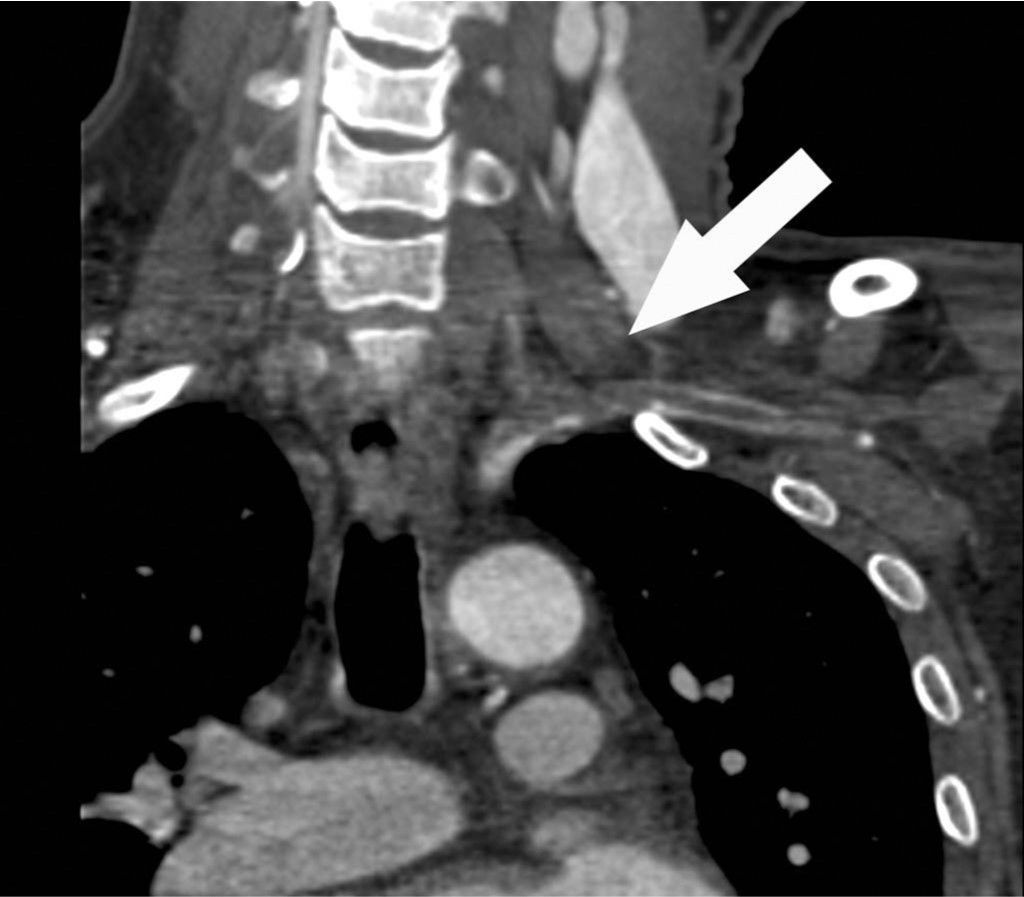

상지 CT 혈관조영술 관상면 영상에서 좌측 쇄골하동맥의 근위부에서 약 7cm에 걸쳐 혈전색전증에 의한 혈관의 부분폐쇄가 확인되고(Fig. 1A, B, C), 혈전색전증은 좌측 추골동맥 근위부로도 연장되어 있음(Fig. 1D).

Fig. 1. A-D

Fig. 1A-D Coronal CT images show a partial thrombotic occlusion at proximal subclavian artery (SCA, arrow in Fig. 1A-C), and proximal vertebral artery (VA, arrow head in Fig. 1D).